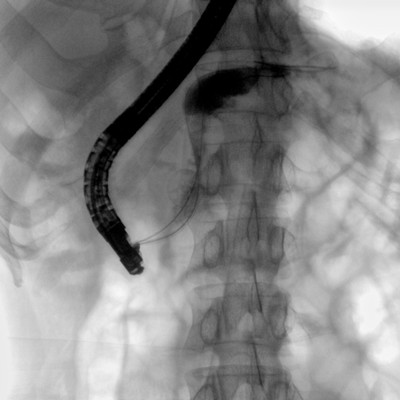

Clinical picture

临床图片

消化内科: ERCP、PTCD、肝脏介入(TACE、灌注)、食管支架等。